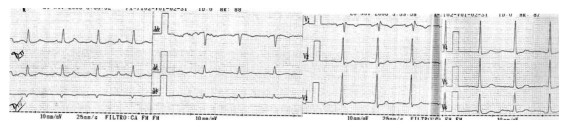

El paciente al completar la tercera etapa a 900 kgmts, con una frecuencia cardíaca de 136 cpm correspondiendo al 88% de la frecuencia cardíaca máxima teórica, presión arterial de 220/120 mmHg, refiere opresión precordial sin irradiaciones, sin disnea ni síndrome neurovegetativo acompañante.

Debido que el dolor iba en aumento se decide detener la prueba, concomitantemente se registra ensanchamiento del QRS y desnivel del ST horizontal de 2.0 mm en V4 a V6 (figura 2).